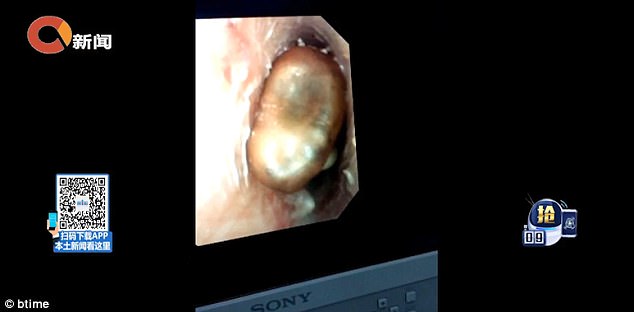

Doktor tempatan mengesahkan butiran di dalam telinga Haohao memang tumbuhan kekacang yang sudah pun bercambah di dalam saluran telinganya.

Pakar telinga, hidung dan tekak, Dr. Zhang Xiao Chun berkata, dia terkejut melihat kacang berkenaan jauh di dalam rongga telinga kanak-kanak itu.

Dr. Zhang berkata, keadaan suhu di dalam telinga sekitar 37 darjah Celsius dan lembap amat sesuai untuk pembesaran kacang.